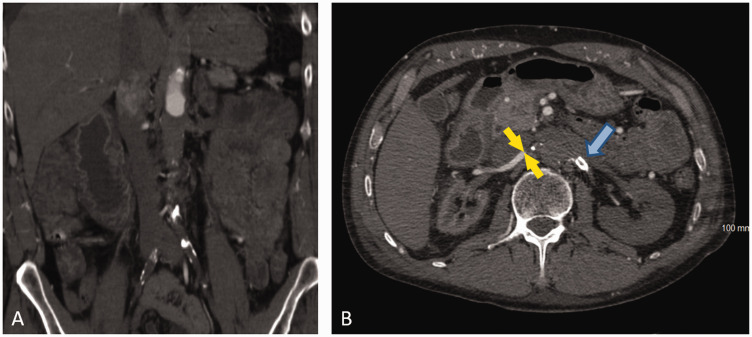

Case report: A 58-year-old male with a history of left renal artery stenosis and stent graft placement presented with symptoms of chest pain, shortness of breath, and flank pain. The patient was admitted to the Intensive Care Unit with the diagnosis of multiorgan failure and subsequent anuria that led to the initiation of hemodialysis. Computed tomography angiography demonstrated an aortic occlusion along with bilateral proximal renal artery occlusion with reconstitution of the mid to distal renal arteries via collateralization. The patient underwent angioplasty with bilateral renal artery stent-graft placement and successful revascularization of proximal renal arteries. Post-operatively, his renal function and urine output improved, and the patient was able to be weaned off hemodialysis along with the benefit of concurrent amelioration of his renovascular hypertension.